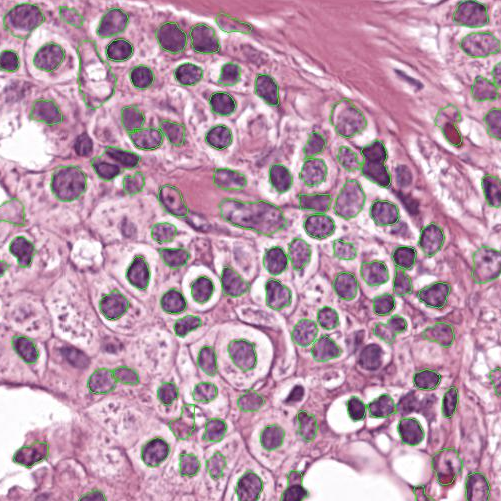

As an essential part of digital pathology, histopathology image analysis is playing increasingly important role in cancer diagnosis, which can provide direct and reliable evidence to diagnose the grade and type of cancer. This paper deals with nuclei segmentation, an important step in histopathological image analysis. The purpose of nuclei semgentation is not only counting the number of nuclei but also obtaining the detailed information of each nucleus. So unlike nuclei detection, here the outputs are the contour of each nucleus instead of only the position of their central points. Hence we can exactly extract each nucleus from the image and make it available for further analysis. For example, the features of the individual nucleus and the distribution of nuclei clusters can be used to grade and classify status of breast cancers [3, 4]. Because of appearance variation such as color, shape, and texture, nuclei segmentation from histopathological images could be very challenging, as illustrated in Fig.1, in which it is very challenging even for human to recognize and segment all nuclei within the images. Fig.1(a) and Fig.1(b) illustrate two histopathological images from different organs. Fig.1(c) and Fig.1(d) are two histopathological images from same organ but have different cancer grade.

Figure 6 shows how our method segments the nuclei step by step. The color variety is well controlled by the color normalization procedure. The prediction result shows clear nuclear areas and nucleus boundaries. In the final segmentation result and ground truth image, each nucleus is represented by a different color.